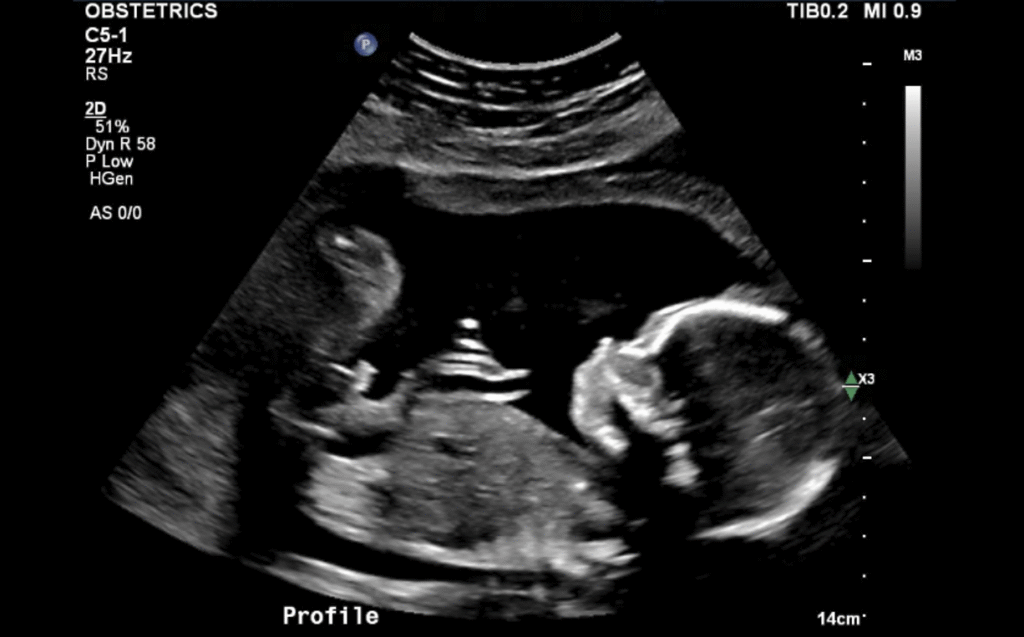

Making sure he stays in the right spot

Look, he’s kicking!